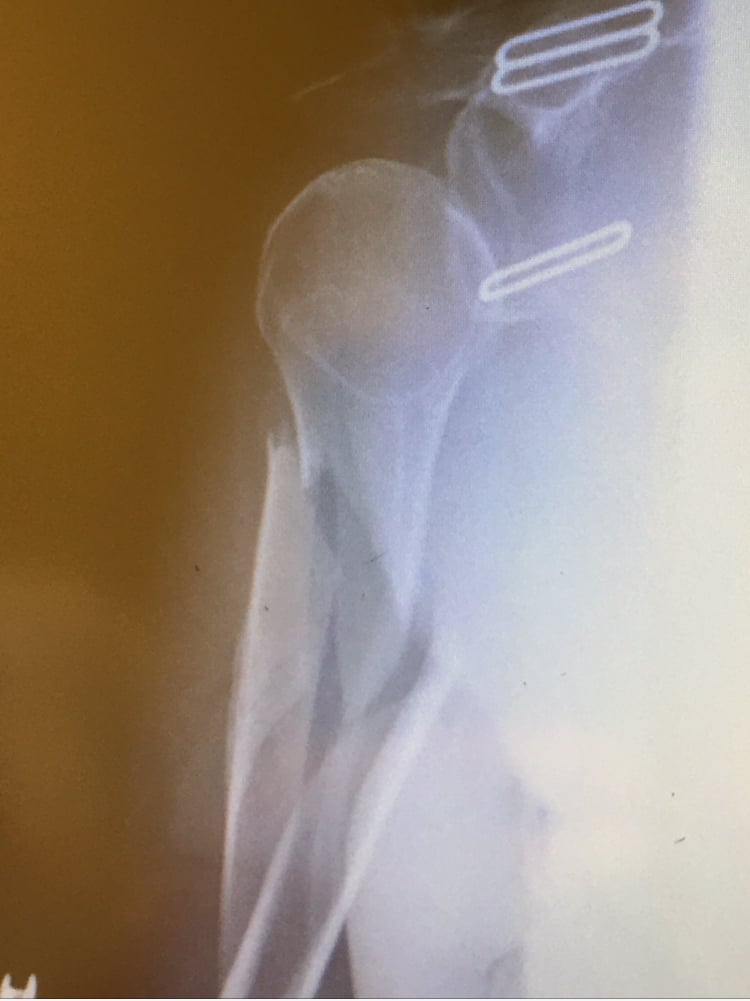

While out jogging one morning in October 2015, I was involved in a hit and run. Emergency Medical Technicians took me to a local hospital where I was diagnosed with a shattered humerus. We decided we only wanted the best care for such a traumatic injury so we got in touch with Esther Shin at Dr. Helfet's office. They could not have been any nicer and accommodating. The entire hospital staff were just amazing from the instant we rolled through the doors through out the entire stay, which was for almost a week. The humerus needed to be put back together with a couple of pins and many screws, as well as the muscle needing to be reconstructed.